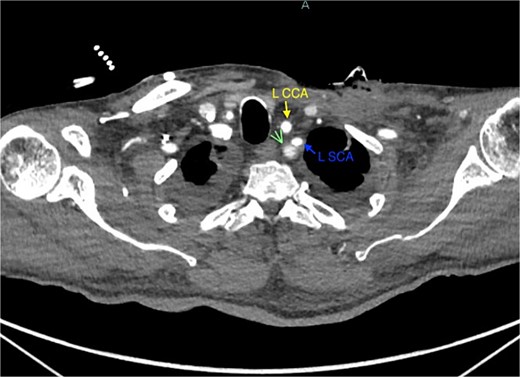

A 67-year-old male with a medical history significant for hypertension, diabetes, coronary artery disease, carotid artery stenosis, osteoarthritis, and 50 pack-year smoking history presented initially to an orthopedic surgery office for evaluation of left shoulder pain after exercising. The patient was found to have an underlying rotator cuff injury and was subsequently treated with cortisone injection. The patient subsequently developed septic arthritis, ultimately requiring incision and drainage of the abscess and resection of the sternoclavicular joint, partial first rib, and partial clavicle. The patient required multiple washouts and debridement procedures, ultimately leading to septic shock and bacteremia requiring close observation in the surgical intensive care unit. A computed tomography angiogram (CTA) of chest was performed at the time and revealed a subcentimeter penetrating ulcer, arising from the proximal left subclavian artery likely secondary to surgical trauma, which was observed nonoperatively given the patient critical status in the intensive care unit (ICU) (Figs 1 and 2). During the ICU course, the patient developed left upper extremity swelling A left upper extremity duplex ultrasound subsequently revealed a nonocclusive deep vein thrombosis of the subclavian vein and also showed resolution of a pseudoaneurysm (PSA) of the subclavian artery. The patient was started on anticoagulation at this time for a deep vein thrombosis (DVT). The patient was ultimately discharged upon resolution of his acute infection to a rehabilitation facility. During the third-month follow-up office visit, the fistulous connection between the subclavian artery and vein was found incidentally on left upper extremity duplex ultrasound (Fig. 3). Physical exam of the patient was otherwise unremarkable with palpable upper extremity pulses and the patient did not appear to have any symptoms related to the fistula including upper extremity swelling or open wounds. The patient was scheduled for an elective repair of the fistula via endovascular stent graft placement. The patient was brought to the operating room, and the radial artery was accessed with a micropuncture device. Radial artery access was our choice to intervene given the location of fistula. When left upper extremity angiography was performed, it revealed a blush of contrast from proximal subclavian artery, revealing a small fistula between subclavian artery and subclavian vein (Fig. 4). Subsequently, a 6 × 29 mm balloon-mounted stent graft was used to cover the fistula. Completion angiography was performed showing adequate seal with resolution of the fistula (Fig. 5). The patient tolerated the procedure well and was subsequently discharged from the hospital the same day. He was started on antiplatelet therapy post-operatively and continued oral anticoagulation for the DVT. The patient was seen in the office at 3-month follow-up, where a repeat duplex ultrasound revealed normal waveforms and velocities throughout the left arm. He was also seen in the office recently, and he is doing well with no new complaints.

Demonstration of pseudoaneurysm of the proximal left subclavian artery on axial image (green arrow: L SCA PSA, blue arrow: left subclavian artery).